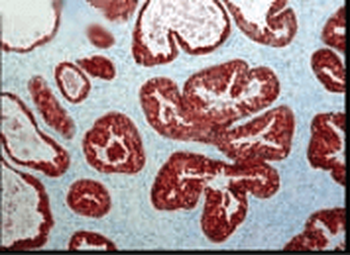

Anti-Cyclophilin A/PPIA Antibody [orb19174]

FC, ICC, IF, IHC, IHC-Fr, WB

Human, Mouse, Rat

Rabbit

Polyclonal

Unconjugated

10 μg, 100 μgCYPA Rabbit Polyclonal Antibody [orb100498]